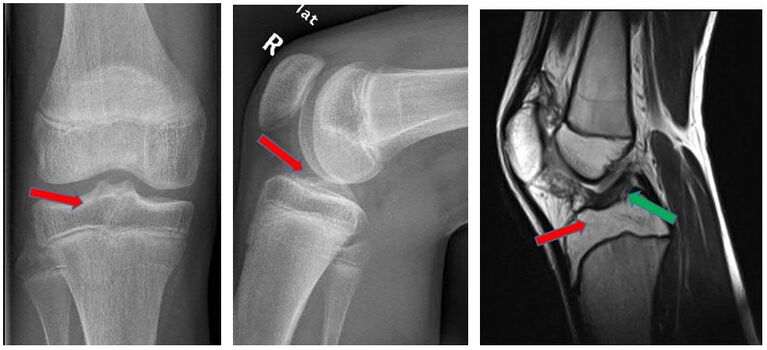

Eine Sonderform der Kreuzbandverletzung ist der knöcherne Ausriss des Bandes. Dabei kommt es bei der Verletzung nicht zu einer Ruptur des Bandes, sonders das Kreuzband reist mit einem Knochenstück ab. Meist ist dieser Ausriss dabei am Schienbeinkopf lokalisiert. Besonders gefährdet sind Kinder und Jugendliche, da bei diesen der Knochen meist weicher als die Bandstruktur ist. Die Symptome und Beschwerden entsprechen einer Kreuzbandruptur. Oft können die Verletzten das Bein nicht richtig strecken, da das Knochenstück einklemmt. Diese Verletzung ist im Gegensatz zu einer Kreuzbandruptur oft auch im normalen Röntgenbild des Kniegelenkes zu sehen. Zur Sicherung der Diagnose und um nach eventuellen Begleitverletzungen zu suchen, erfolgt oft ein MRT und manchmal auch eine Computertomographie (CT).